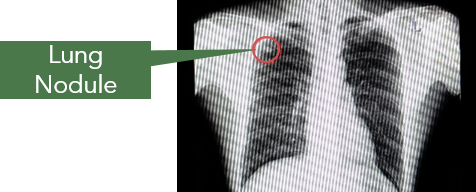

How are Lung Nodules Diagnosed?

Lung nodules are commonly seen on CT scans performed for other reasons. Sometimes, they can be detected on chest radiographs if they are larger in size.

It is not always possible to determine the cause of the lung nodules from CT scans alone. Biopsy, a procedure to obtain small samples from the nodule for further evaluation, may not be successful if the nodule is too small in size.